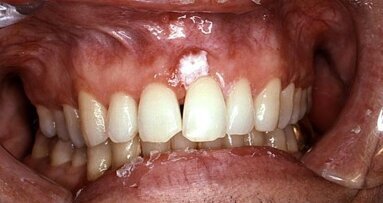

При последната среща беше поставена окончателната хибридна винтово-фиксирана протеза. Окончателната протеза се състоеше от CAD/CAM титанова рамка, завинтена към всички импланти, и три монолитни циркониеви протезни сегмента, залепени отгоре (фиг. 18а–в). Беше оценена оклузията и пациентът беше включен в четиримесечна програма за поддържане. При последната контролна визита (една година след поставянето на имплантите) всички импланти бяха успешни и пациентът беше удовлетворен от новата протеза (фиг. 19–22).

Фиг. 21: Едногодишно проследяване, лицев изглед.